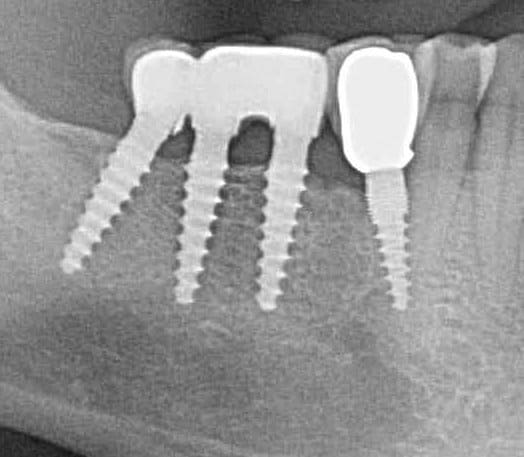

Bonjour flicflac je suis désolé de ma réponse tardive, oui il est vrai que ce n est pas beaucoup documenté ... je serai un menteur de dire que que je n ai jamais perdu des implants, surtout entre la 2eme et 8eme semaine après l implantation.Un échec vraiment à cause de la perte osseuse et avec le même process cela est arrivé une fois avec une madame, où l´os était encore infecté ( avant la chirurgie),mais après l ´échec (c était à la position 35) on a pu laisser le bridge. Malheureusement je n ai pas toutes les photos ici à Mallorque sur mon PC portable. Ci dessous une photo après 10 ans 46 47 et les implants au maxillaire.

Oui ca semble ....sur la opg radio tu peux voir la situation seulement deux semaines après l´implantation immédiate 34 jusqu´à 36 et 45, les derniers 2 photos montrent la même situation après un an ( où on a enlevé la supra construction pour un contrôle). Sur ce cas je voulais montrer la bonne régénération osseuse et de la gencive.